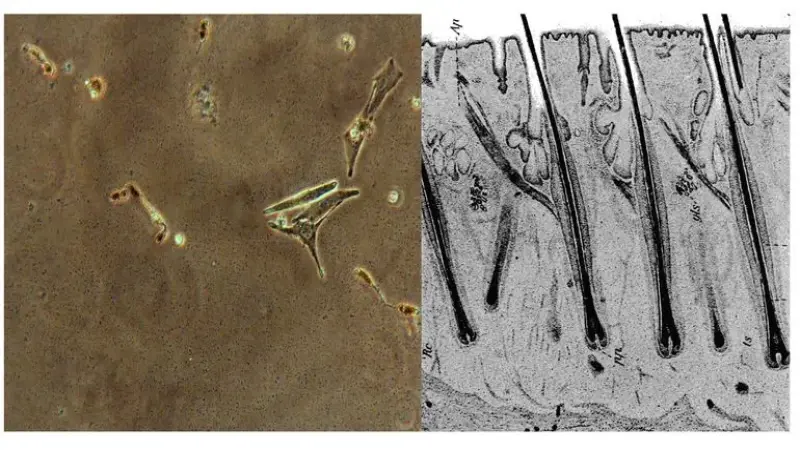

Lead researcher of this published study Qi Sun says, follicular oncogenic melanocyte stem cells, which have been found in the mouse model, can establish melanomas. Stem cells are the underlying cells of the human body formed during the embryo stage to help develop various other cells. Qi Sun says that melanomas found during the research will be useful to identify new ways of diagnosis and treatments for melanoma. But what it needs is human trials for further confirmation to treatment.